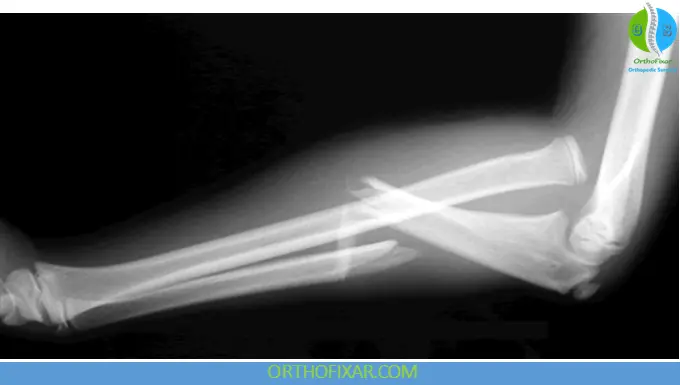

- X-rays (AP and lateral views) of forearm including elbow and wrist

- Key diagnostic sign:

- The radial head does not align with the capitellum on all views